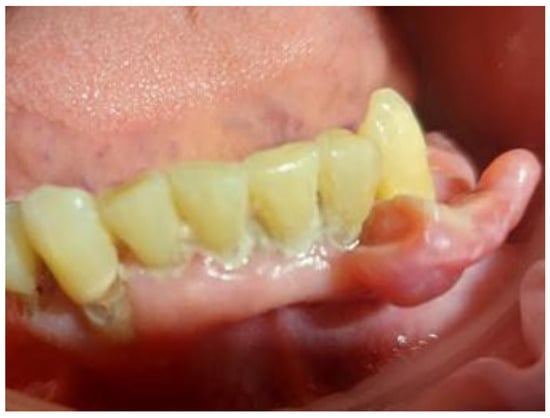

2. Case Presentation